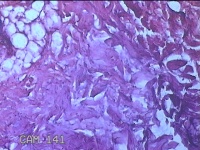

性别

男

年龄

50岁

临床诊断

皮脂腺囊肿

一般病史

发现左侧膝部包块8年余,无明显疼痛及不适。

标本名称

左侧膝部包块

大体所见

灰白暗红色组织3.3x2.3x0.8cm一块,表面带梭形皮肤3.5x1.5cm,皮下见包块3.3x1.5x0.8cm一个,切开包块呈实性,切面灰白粉红色,质软。

图1